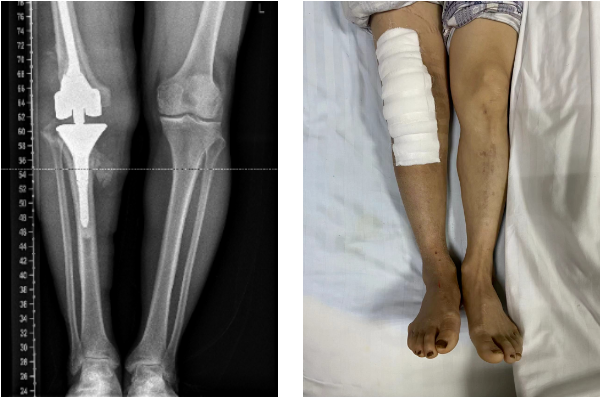

经过充分的术前准备,在手术室及麻醉科医护人员的配合下,成功实施了定制旋转铰链式人工全膝关节置换术,为患者重塑膝关节。术后给予抗感染、预防血栓等治疗,同时加强功能锻炼,在康复治疗师的指导下,术后一周患者就可以自行拄拐下床行走。

患者的术后情况